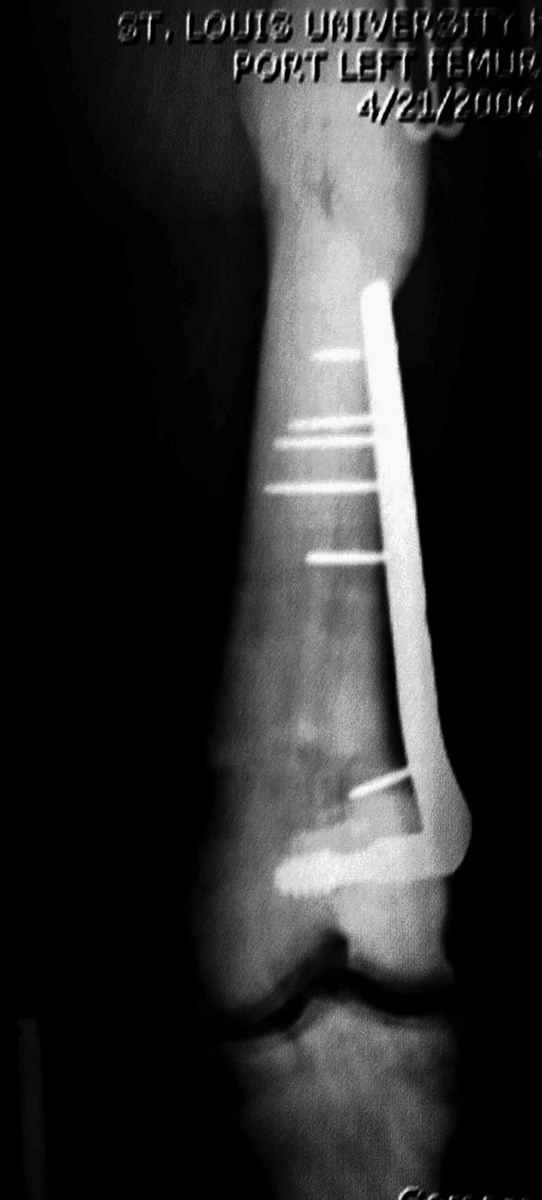

Здесь у меня дополнительные снимки с большим разрешением и в разных режимах, а то те дигитал снимки совсем очень блеклые, может, эти изображени изменят выбор тактики

После неудачной попытки скелетного вытяжения в первом мед.учреждении, после осмотра снимков и изучения истории, поставили диагноз “Остеопетроз” или мраморная болезнь, редкая наследственная костная паталогия, где имеется нарушение формации остеокластов.

Конечно, было бы идеальным применение интрамедуллярного остеосинтеза, но учитывая прежний собственный опыт (лечил перелом бедра) и

публикации, предупреждающие о трудностях при обработке кости (иногда из-за неподготовленности инструментария результатом была неадекватная фиксация перелома, или перенос операции из-за фактора усталости оперирующего персонала), решили применить пластину (и в этом же случае был выбран Synthes plate, так что представитель за два дня

зароботал... на десерт тоже).

Заказаны были дополнительные различные дрели, и на следующий день, усиленной бригадой, больного прооперировали, потратив на каждое отверстие около 25-35 минут, хотя сверлили с охлаждением по нарастающей по диаметру сверл и с их заменой каждые 2 мм сверления.

Теперь стоит задача со сращением перелома, из-за отсутствия литературных данных по применению костных стимуляторов при остеопетрозе, и не зная как поведет в этой среде Grafton, все таки надеюсь, что даст толчок к стимуляцию, решил применить пастообразную деминерализованную костную матрицу, расположив спереди между отломками.